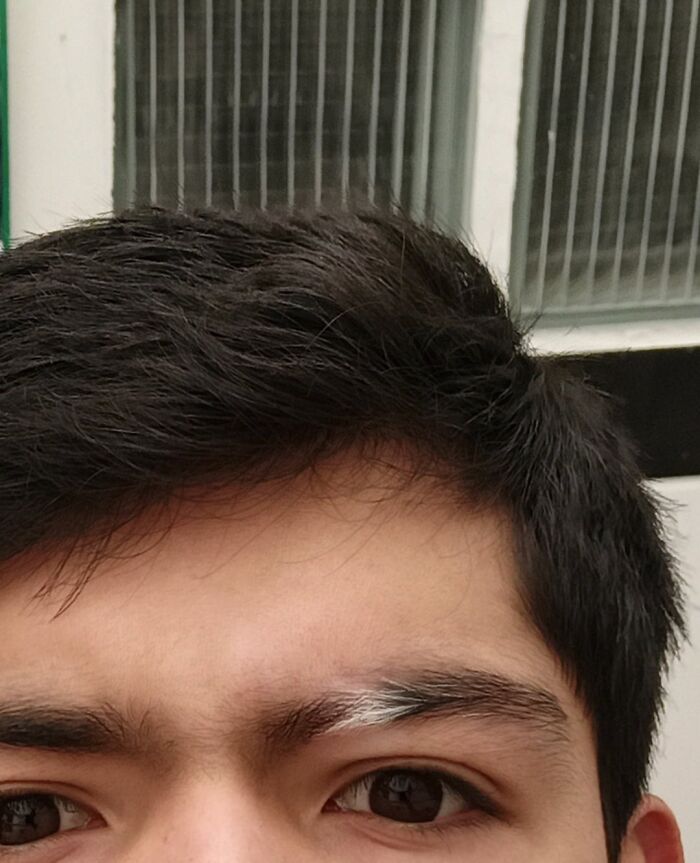

Is This Vitiligo Or What Another Disease Turns Your Eyebrow White?